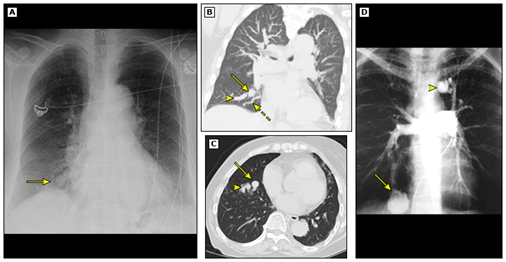

在形态上,肺结节分为实性(如图1)或亚实性;亚实性结节又细分为大名鼎鼎的纯磨砂玻璃结节,即pGGO(无实性成分)(如图2)和部分实性结节(磨玻璃加实性成分)(如图3)。

图2 纯磨砂玻璃结节(类似于磨砂玻璃,朦胧美)

图3 部分实性结节(即磨玻璃里面有实性成分)